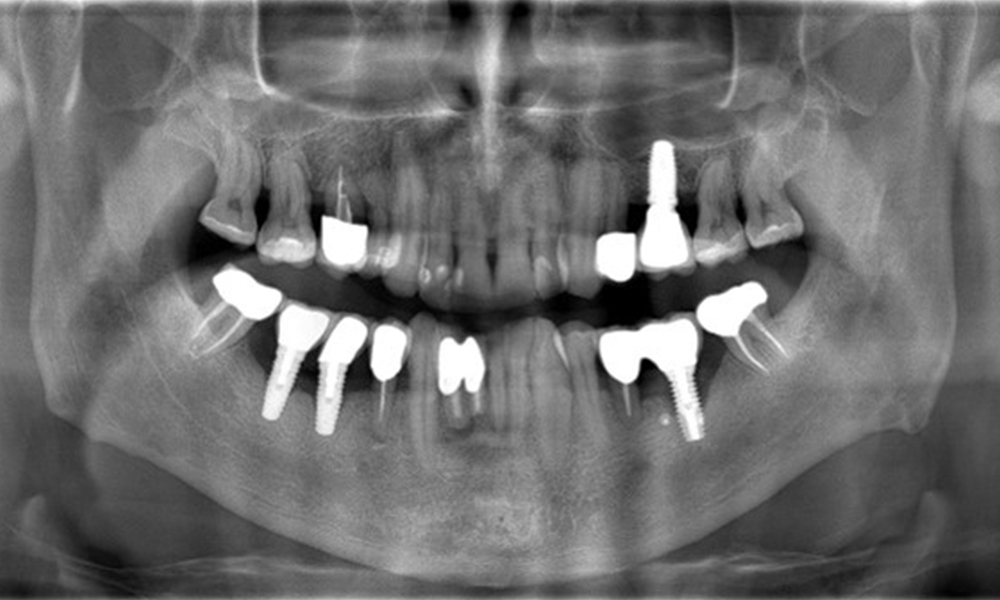

Ein 52-jähriger Patient stellt sich zur Präventionssitzung vor. Der Patient hat keine Allgemeinerkrankungen und nimmt keine Medikamente ein. Er hat verschiedene zahnärztliche Versorgungen und zudem zwei aktive kariöse Läsionen. Außerdem verfügt der Patient über vier Implantate (2., 3. und 4. Quadrant). Es zeigt sich eine parodontale Vorerkrankung (Stadium IV, Grad B). Derzeit herrschen stabile parodontale Verhältnisse, lediglich am Implantat regio 36 zeigen sich Sondierungstiefen (ST) von 5 mm. Zudem lässt sich eine Gingivitis feststellen.

Röntgenaufnahme zeigt Verlauf des Knochenabbaus

"Die Röntgenaufnahmen zeigen den Verlauf des Knochenabbaus. OPG vom 29.06.2020 (links) und OPG vom 26.02.2024 (rechts)

OPG: 26.02.2024 ZF: 18.01.2024